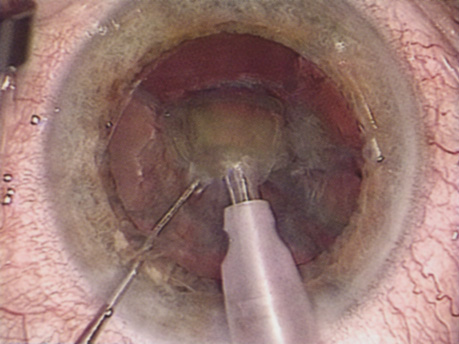

WHITE CATARACT

The introduction of innovative adjunctive devices was able to improve the management of challenging cases. The capsular tension ring introduced independently by Tsutomu Hara37 and Toshiyuki Nagamoto38 in Japan was identified as a major weapon in managing zonular weakness by Ulrich Legler and Bernd Witschel of Germany.39 The CTR came to the United States in 1993,40 after which modifications by Robert Cionni,41 Iqbalk Ahmed and Alan Crandall,42 and Burkhard Dick were developed. Iris reconstruction had been primarily limited to suture techniques developed by Malcolm McCannel43 and later Steven Siepser.44 The prosthetic irides were introduced by German surgeons, Ranier Sundmacher45 and Volker Rasch,46 and brought to the United States by Kenneth Rosenthal and then Robert Osher in 1996.47 Although many devices had been developed to mechanically open the small pupil, it was the stretch technique developed by Luther Fry that greatly simplified these difficult cases.48 Improving visibility by staining the anterior capsule of the white cataract was introduced by Masayuki Horiguchi from Japan (ICG)49 and Gerritt RJ Melles from The Netherlands (Trypan Blue).50